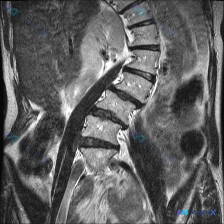

- 疑问是「从这张MRI能不能看到脊柱侧弯」

- 提供的是腰椎MRI T2加权矢状位图像

- 椎间盘:腰椎各节段T2信号明显降低(脱水退变),L4/L5、L5/S1椎间隙狭窄,且这两个节段有椎间盘后突、压迫硬膜囊

- 椎体:腰椎生理前凸曲度变直,L4、L5边缘骨质增生,终板信号略不均但无急性水肿

- 椎管:L4/L5、L5/S1节段椎管狭窄,黄韧带增厚,小关节增生硬化

- 序列:椎体连续性尚可,无明显滑脱